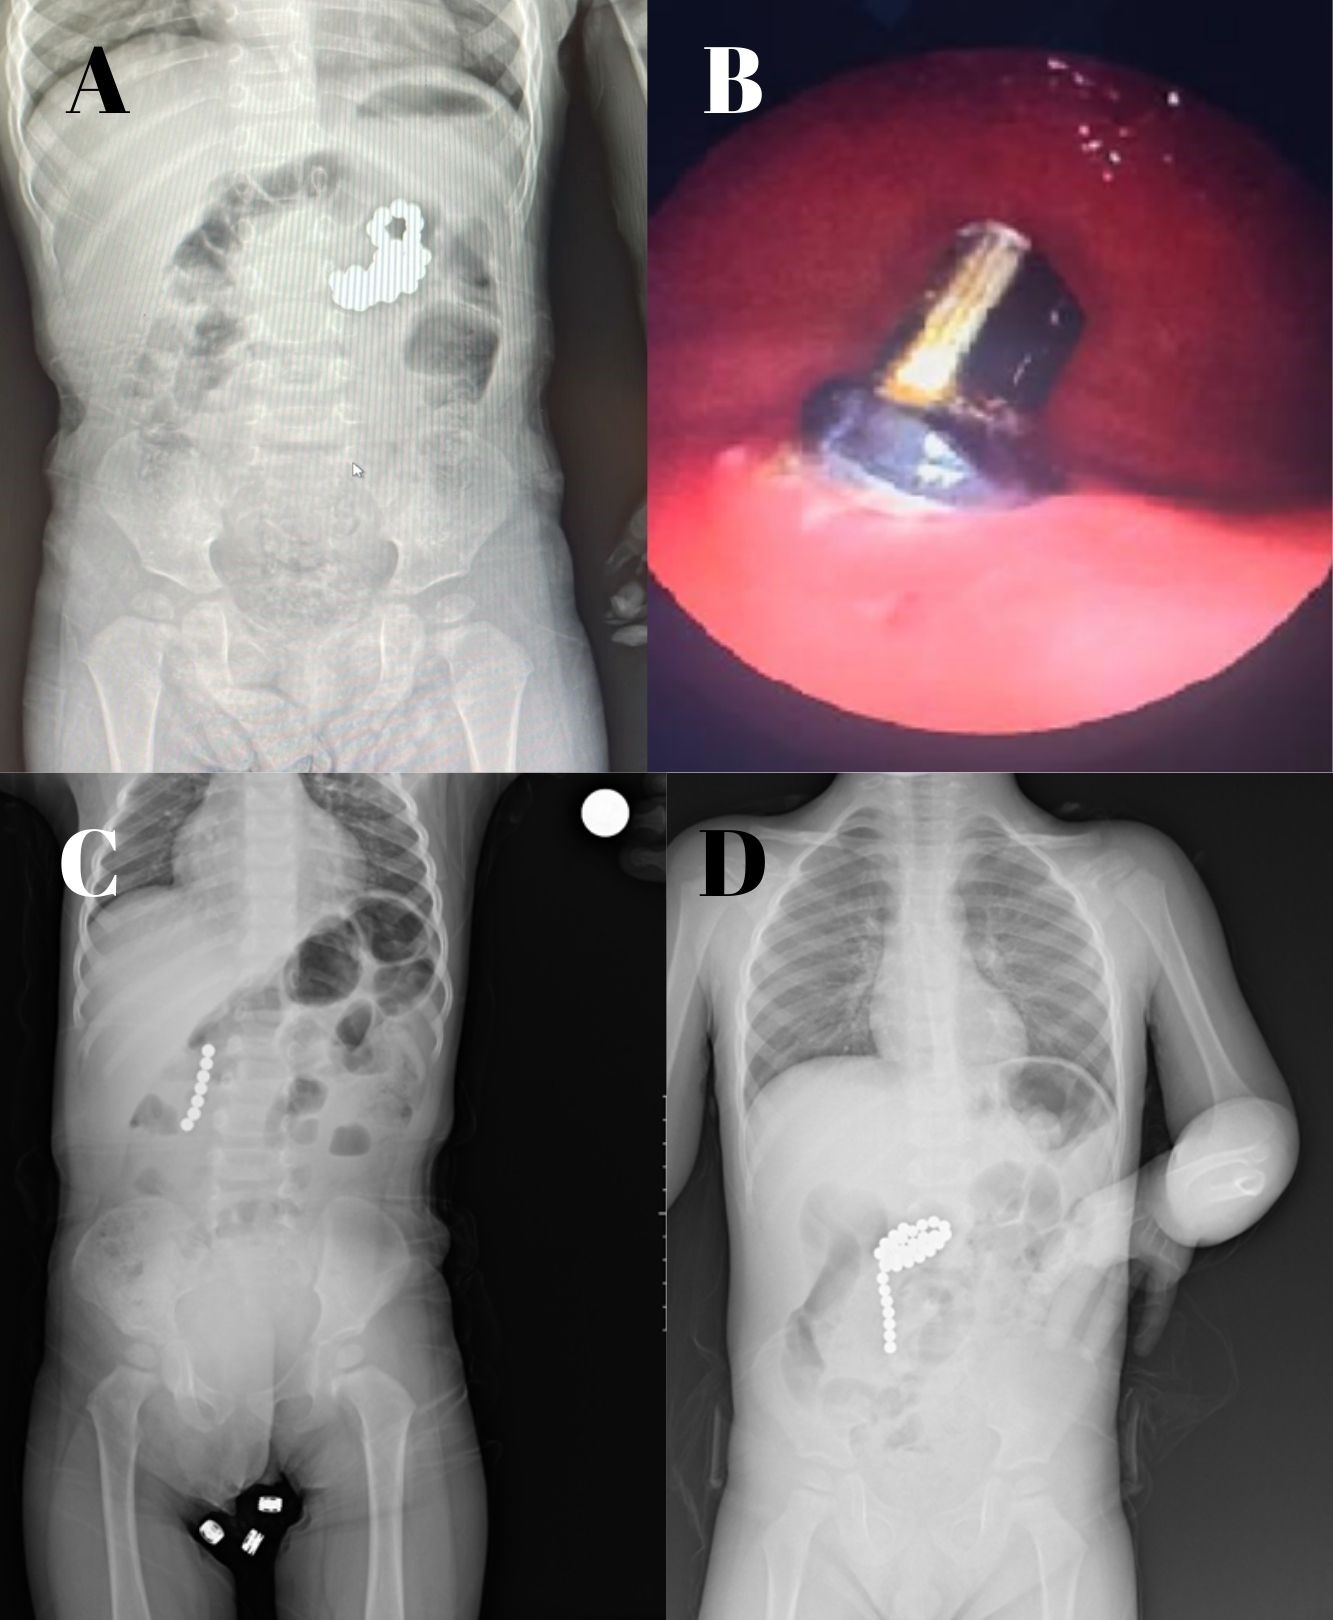

Among the patients who underwent endoscopic procedures, seven received esophagogastric interventions, while one underwent a colonoscopy. In one case, a single magnet located in the initial esophageal stricture was extracted via esophagoscopy. In six patients, magnets ranging from 1 to 41 were identified in the stomach, all of which were successfully removed through esophagogastroscopy (Fig. 2A). In one patient, a magnet was located in the stomach, with another found in the jejunum, adhering to the stomach magnet (Fig. 2B). The portion of the magnet attached to the jejunum, which was removed from the stomach by gastroscopy, passed through the digestive tract spontaneously the following day.

Five patients required surgery. Each patient underwent laparotomy; with the exception of one patient whose surgery was incidental. The indications for surgery included peritoneal signs, intestinal perforation, or intestinal obstruction. A 12-month-old male patient who ingested seven magnets presented with two perforations in her duodenum (Fig. 2C). A two-year-old female patient who ingested twenty-seven magnets presented with two perforations in the stomach and jejunum, which were surgically repaired using primary closure (Fig. 2D). A ten-year-old male patient who ingested 28 staples after swallowing a magnet developed an ileoileal fistula and internal herniation (Fig. 3A1-A3). A three-year-old male patient who ingested two magnets presented with an ileoileal fistula and a perforation (Fig. 3B1-B2). Primary repair was performed in three patients and resection in one patient. In one patient, a magnet found incidentally in the cecum was removed from the appendix and an appendectomy was performed. There were no postoperative or postprocedural complications, and all patients were discharged after recovery. No deaths occurred during the study period.